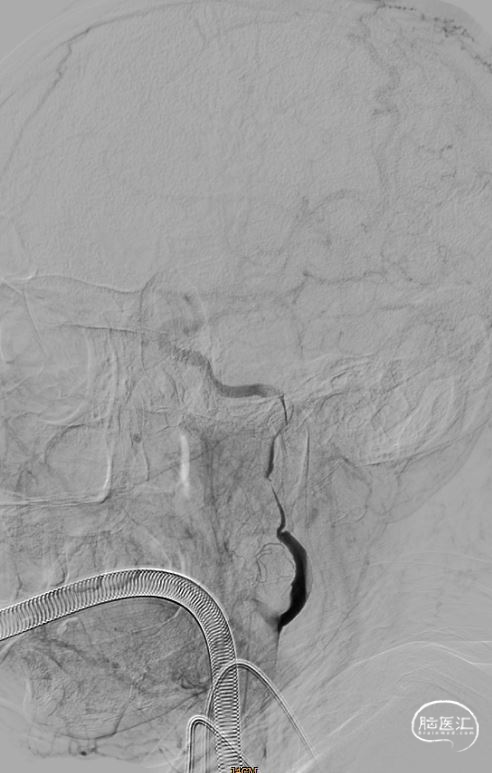

右股动脉处置入8F 股动脉鞘,分别沿鞘送入泥鳅导丝、5FH1动脉造影导管造影提示右侧颈内动脉C1段闭塞,考虑右侧颈内动脉夹层。

路径图下沿导引导管送入6F 颅内支持导管(6F*125cm)+微导管+微导丝(0.014*200cm)组合,在路径图引导下,将支持导管先端置于右侧颈内动脉C1段,造影显示前交通动脉有代偿。